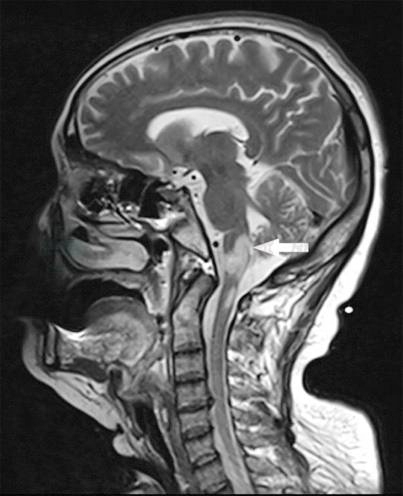

图4 复查颅脑、颈髓MR

引自:主编:.消化系统疑难疾病诊疗思维及病例解析.第1版.ISBN:978-7-117-28669-5

患者呕吐,需要排除所有可能的器质性疾病后,才考虑功能性疾病所致。胃镜、肠镜、全消化道造影、肿瘤标志物、胸腹盆平扫及增强CT可以排除消化道器质性疾病。肝肾功能、血糖、甲状腺功能正常,可以排除常见代谢和内分泌系统疾病。患者病史较短、急性起病,无口干、眼干、皮肤发紧、皮肤红斑、关节疼痛等症状,且风湿全套检查未见异常,可排除风湿免疫疾病所致呕吐。反复追问病史得知,患者并无药物服用史、毒物接触史。患者为青壮年女性,出现严重的肺部感染,且伴有言语不清、吞咽呛咳等症状,应考虑颅脑病变,特别是延髓病变所致。当地医院颅脑MRI虽未见异常,在患者病情加重时应复查。复查颅脑、颈髓MRI提示延髓低信号病变,结合患者脑脊液APQ-4Ab阳性。最终明确诊断。

视神经脊髓炎。